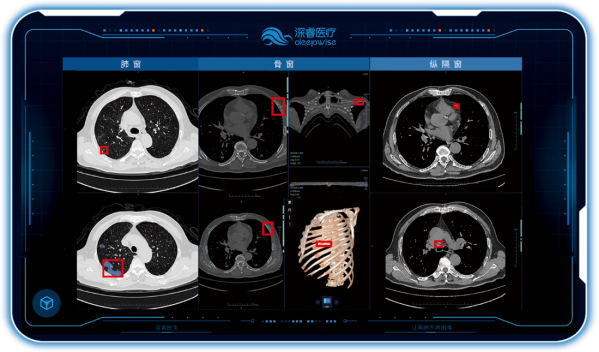

深睿医疗南区产品经理李满梁在介绍本次人工智能项目时指出,江西省胸科医院此次引入的胸部CT AI医学辅助诊断系统,是深睿医疗针对各类胸部疾病诊断推出的一站式解决方案,完全模拟医生日常诊断流程,实现完整的肺窗、骨窗、纵隔窗的三窗联动,针对包括肺部病变、气管和支气管病变、胸膜病变、食管病变、心脏血管病变、胸部外伤等多种胸部疾病,提供智能的诊疗新模式。

在肺部疾病诊断中,除了常见的肺结节、肺炎、胸部骨折等相关病灶征象的检出,还可以提供肺结节良恶性提示、危急疾病预警、多发结节智能随访等增强功能。同时通过肺窗与纵隔窗联动,系统还可对胸膜病变,如胸腔积液,气胸,胸膜增厚等疾病或征象同时检出与提示,提高胸膜病变检出敏感性,并对相关征象进行定量分析,为医生判断疾病的严重程度,制定治疗方案提供详细的诊断依据。

深睿医疗的胸部CT AI医学辅助诊断系统除了常见的呼吸系统疾病,也可对其他胸部疾病提供智能诊断。比如食管裂孔疝,是一种常见的消化系统疾病,腹腔脏器通过扩大的食管裂孔进入胸腔,轻者有胃灼热、反酸等,重者会出现吞咽困难等症状。这类裂孔较小时无需治疗,较大时需要药物或手术治疗。通过肺窗与纵隔窗联动,深睿医疗的AI辅诊系统在对一位肺炎患者的胸部CT诊断中,同时检出提示了食管裂孔疝。三窗联动机制,保证了对患者的一次胸部CT检查中,即可提供肺窗、骨窗、纵隔窗多种疾病与征象的全面检出与智能分析,大大节省了检查的时间与费用,提升胸部疾病的检出率。

深睿医疗的胸部CT AI辅诊系统,三窗联动贴合医生临床诊断模式,用创新的人工智能技术优化工作流程,助力医生提升诊断效率、改善患者就医体验。